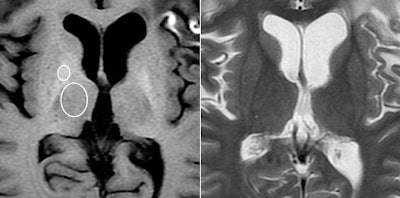

High signal intensity is common in the dentate nucleus and globus pallidus regions of the brain on unenhanced T1-weighted MRI scans, noted lead author Dr. Tomonori Kanda, PhD, and colleagues. Previous research has shown that high signal intensity in the dentate nucleus is associated with a history of brain irradiation or multiple sclerosis, while high signal intensity of the globus pallidus has been linked to a number of conditions, including hepatic dysfunction, calcification, and neurofibromatosis.

Kanda and colleagues also noticed high signal intensity, or hyperintensity, in these two regions in patients who have had more than one administration of gadolinium-based contrast agents.

The analysis showed a significant correlation between the number of previous contrast administrations and signal intensity in the dentate nucleus and the globus pallidus, according to the researchers. Hyperintensity was significantly greater in patients who had received contrast, compared with those who received unenhanced scans.

Increased signal intensity in the dentate nucleus and globus pallidus on unenhanced MRI may be due to the number of previous gadolinium-based contrast administrations, Kanda and colleagues noted.